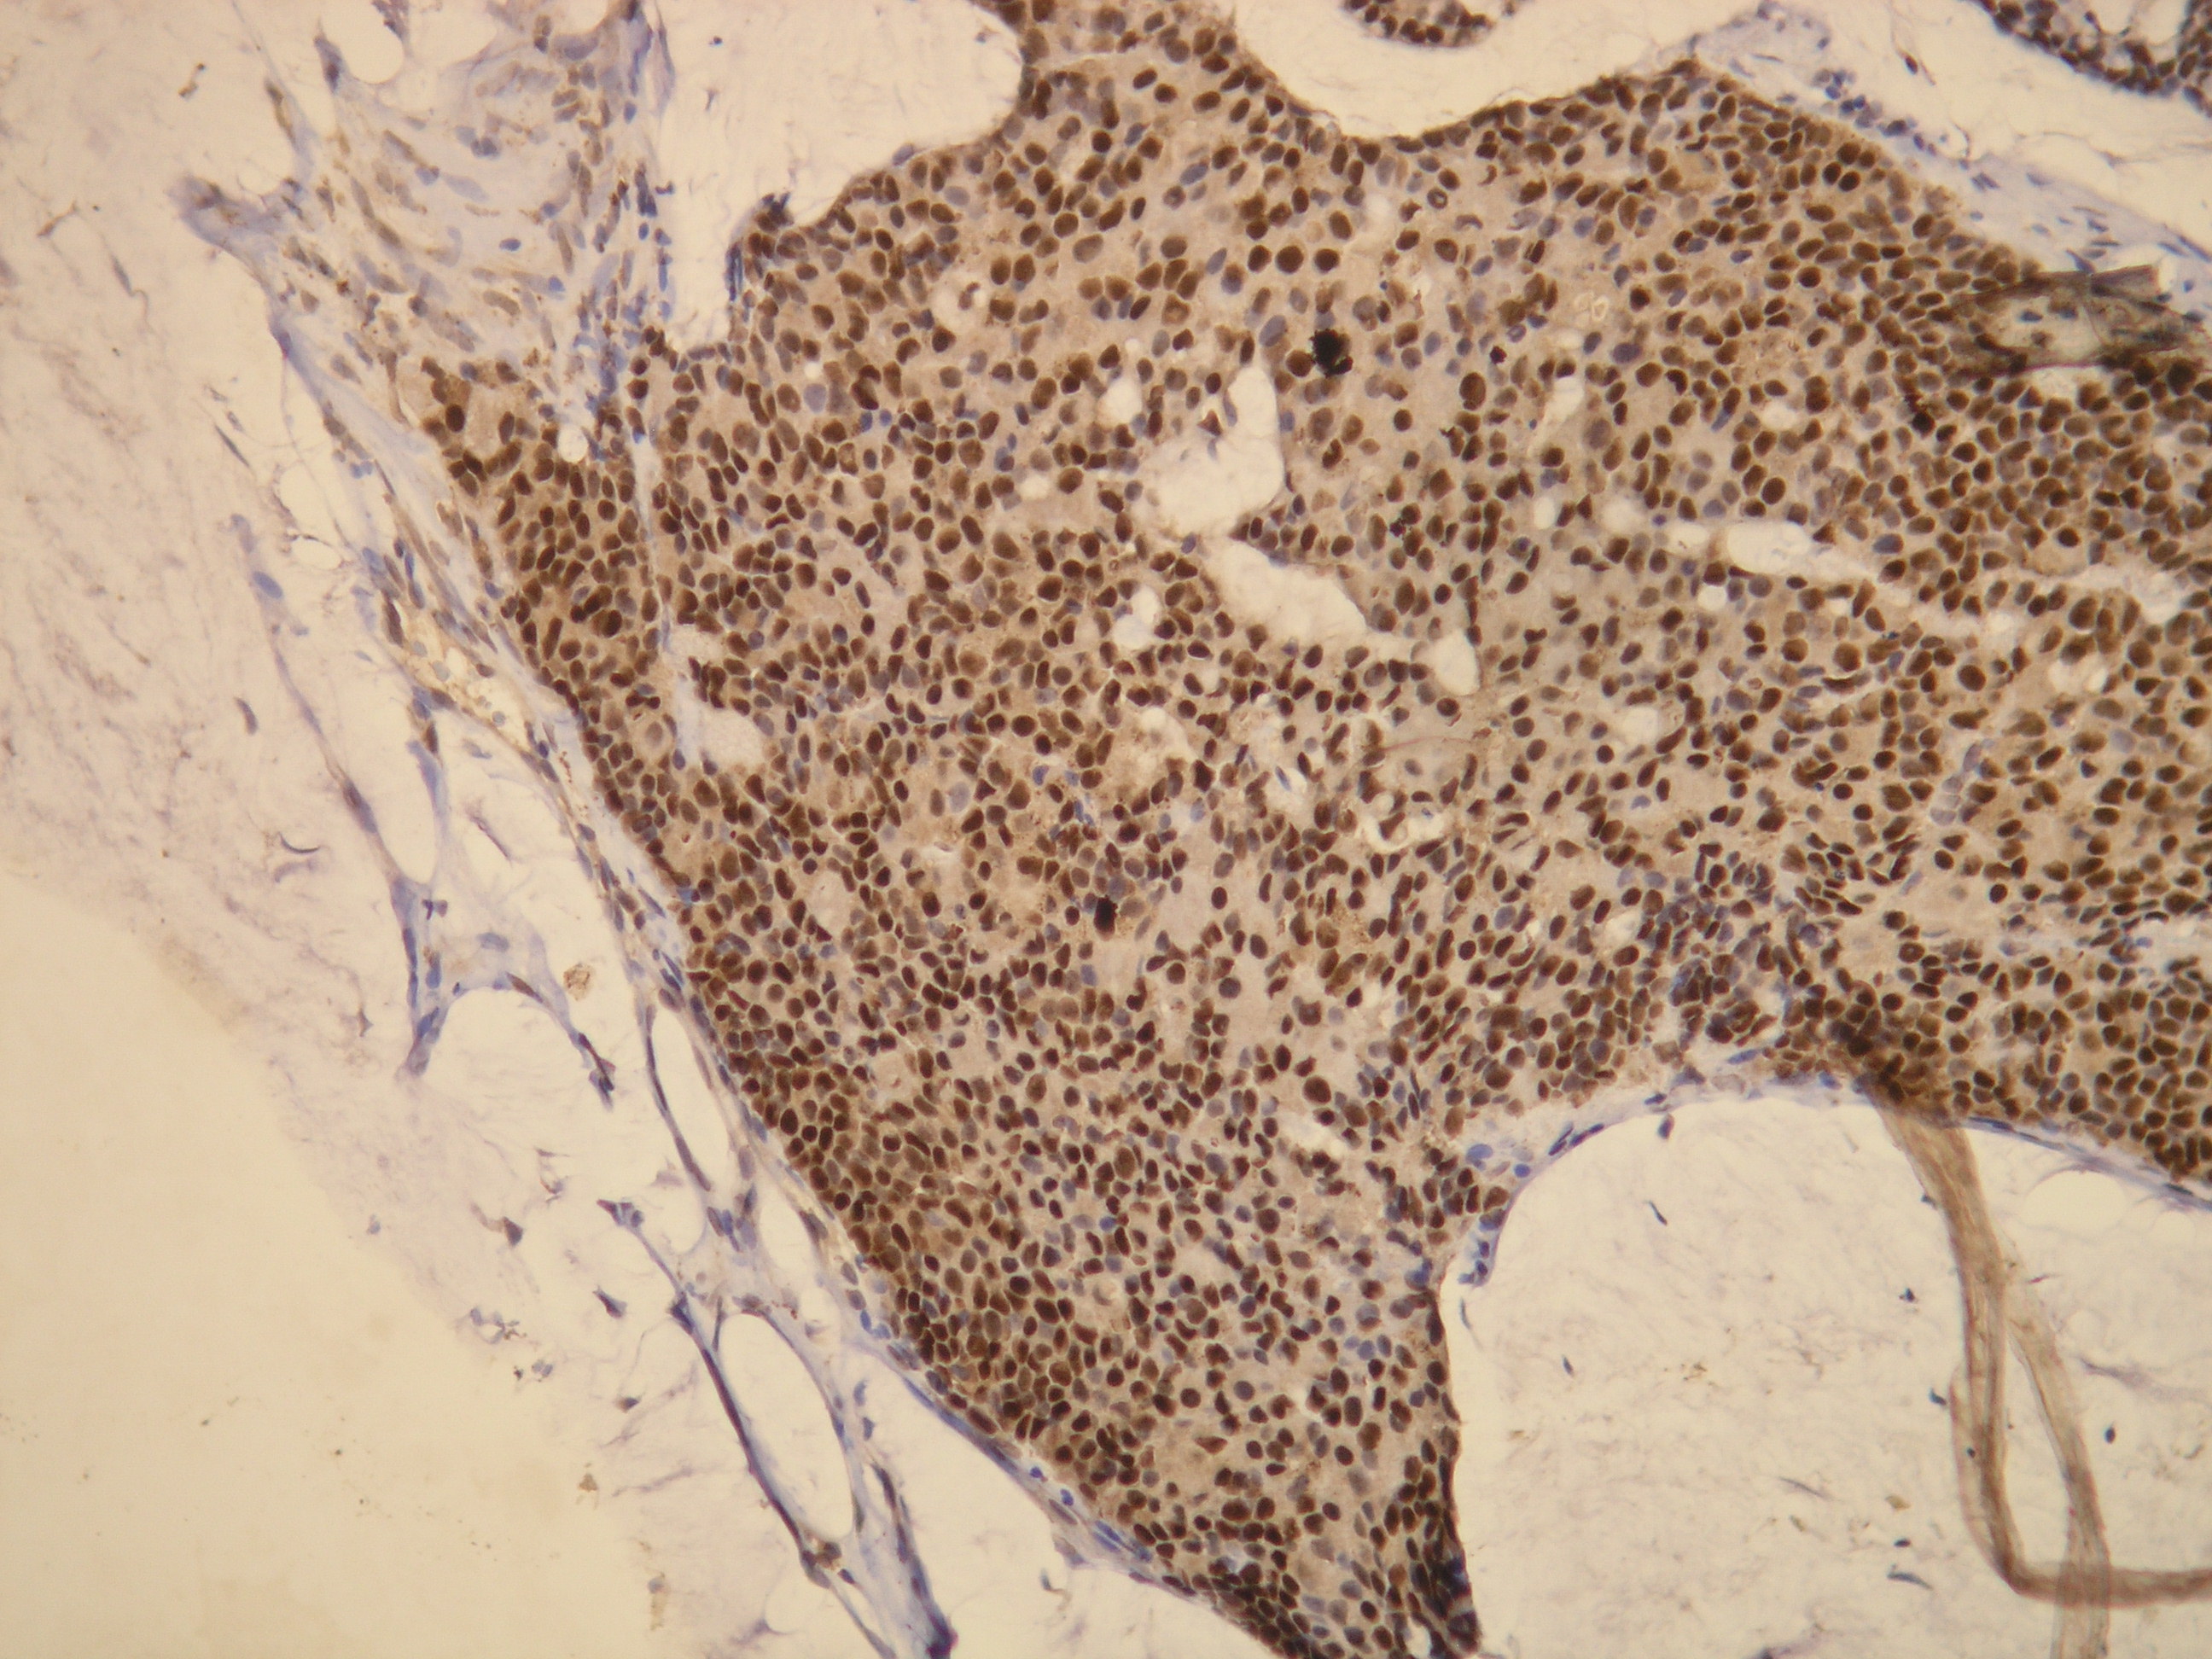

Anti-ER (Estrogen receptor)

IHC-P, riedenie 1:100

db053